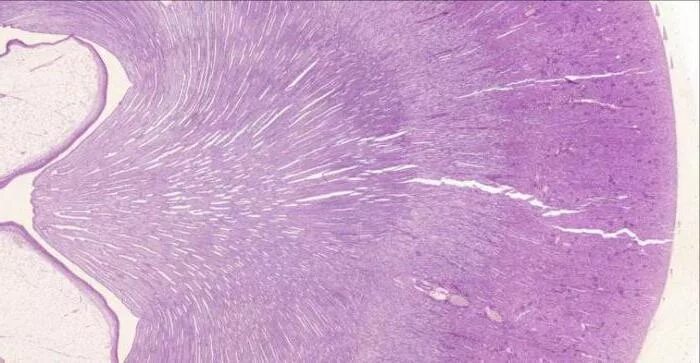

Гистология почки